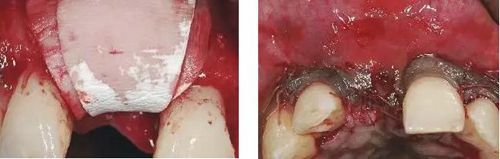

圖8、從上腭獲取結(jié)締組織縫合在黏骨膜瓣上,進(jìn)行軟組織增量。為了使得黏骨膜瓣充分減張情況下關(guān)閉,應(yīng)該使用瓣的分層技術(shù)。使用6-0或者5-0的可吸收線縫合關(guān)閉傷口。4個(gè)月后進(jìn)行二期手術(shù)時(shí)通過分裂瓣技術(shù)將色素沉著的牙齦向冠方復(fù)位以恢復(fù)其原來的自然外形(在此沒有展示)。

圖9、種植體植入5個(gè)月:種植體到唇側(cè)骨板的距離仍然大于2mm,這對于形成長期穩(wěn)的美學(xué)效果有很重要的作用。